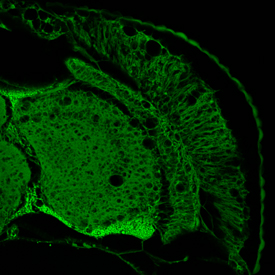

Neurodegenerazione nel cervello di un moscerino della frutta. (Fonte: © VIB 2014)Patrik Verstreken (di VIB / KU Leuven) dice: "Questi risultati inattesi ci offrono una nuovo approccio della ricerca nella comunicazione tra le cellule cerebrali. Riteniamo che nel tempo dovrebbe essere possibile aiutare i pazienti con mutazioni nel gene TBC1D24, inibendo in parte il trasporto ai lisosomi (scompartimenti della cellula che digeriscono varie molecole)".

Patrik Verstreken ed i suoi colleghi hanno sviluppato dei moscerini della frutta con mutazioni nel gene Skywalker, la versione del moscerino della frutta del TBC1D24. Questi moscerini della frutta mostrano sintomi simili a quelli dei pazienti con disturbi cerebrali.

Patrik Verstreken spiega: "Questi moscerini della frutta sono un modello adatto non soloper studiare quello che va male nel cervello, ma anche per esplorare come questo può essere affrontato; ad esempio stiamo cercando di ridurre o eliminare i sintomi nel moscerino della frutta con mutazioni nello Skywalker introducendo ulteriori modifiche al loro DNA. In caso di successo avremo nuovi punti di partenza per la nostra ricerca sulle neurodegenerazioni".